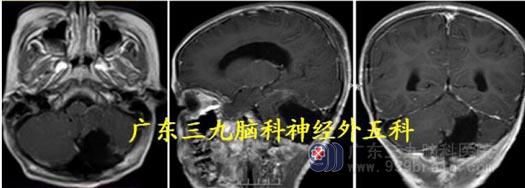

头颅MR:四脑室-脑干背侧示不规则囊实性占位病变呈长T1 长、短T2 混杂信号,FLAIR 序列呈高低混杂信号,增强后明显不均匀异常强化,范围约64.6mm×36.3mm×44.9mm,部分凸入上段椎管。考虑室管膜瘤可能性大。

头颅CTA:脑干背侧-四脑室区占位性病变,其周围血管较多并邻近血管受压。